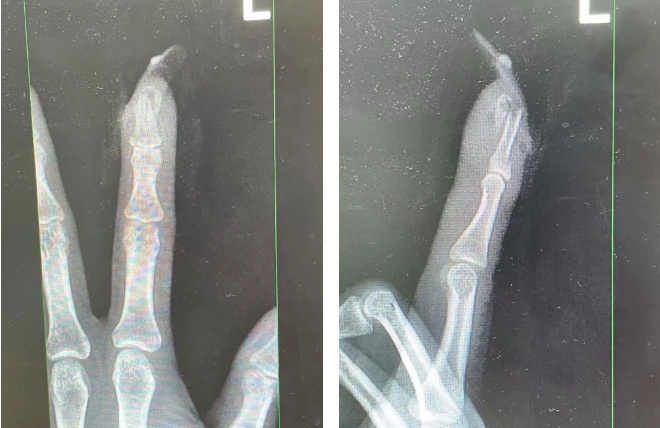

王女士受伤手指的X光影像。图源:杭州市临平区中西医结合医院